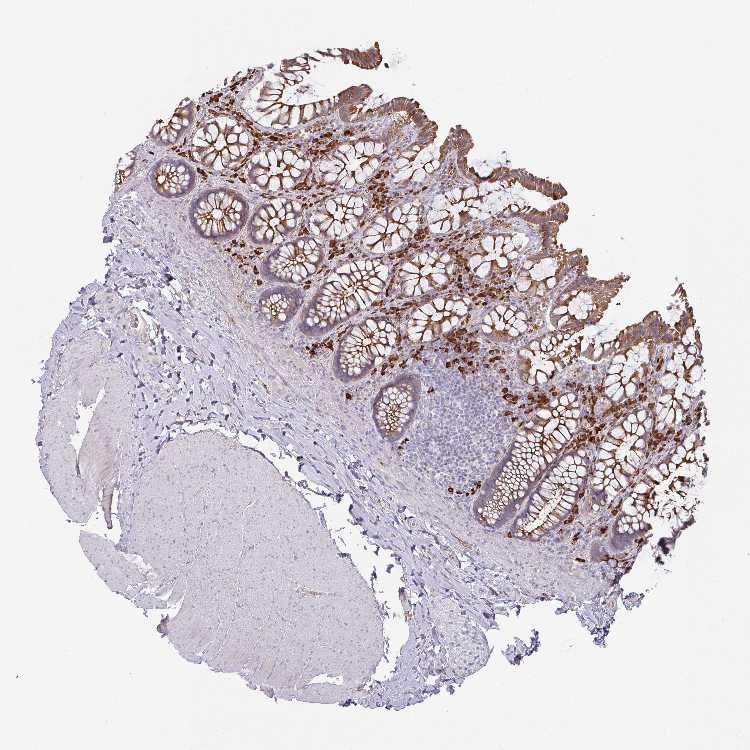

IL4R